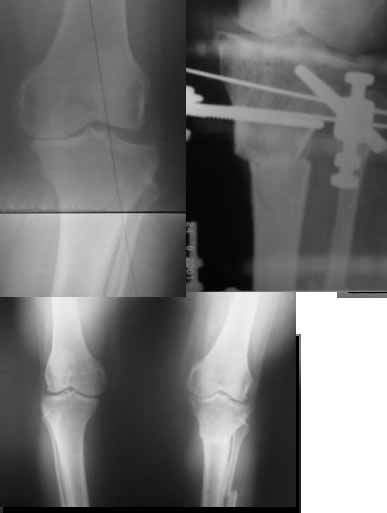

AC> Вот, с учетом и без учета, и на разных уровнях...

AC> Саша Артемьев, может, для данного случая свой вариант нарисуешь?

Из приведнной схемы не совсеим понял что означают разноцветные линии.

И зачем латерализация периферического фрагмента. Я всегда делаю медиализацию. См схему. И для данного случая медиализация подходит как нельзя лучше.

Картинки - в приложении.Будут вопросы - готов ответить.

Ещё картинка - схема. Хотя у Соломина всё написано.

Вот ещё картинки, которые отправлял в Ортопод. Коррекция кривизны и удлинение на 3 см.